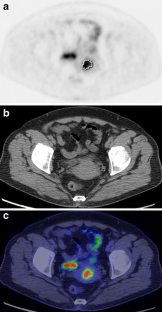

Fig 1